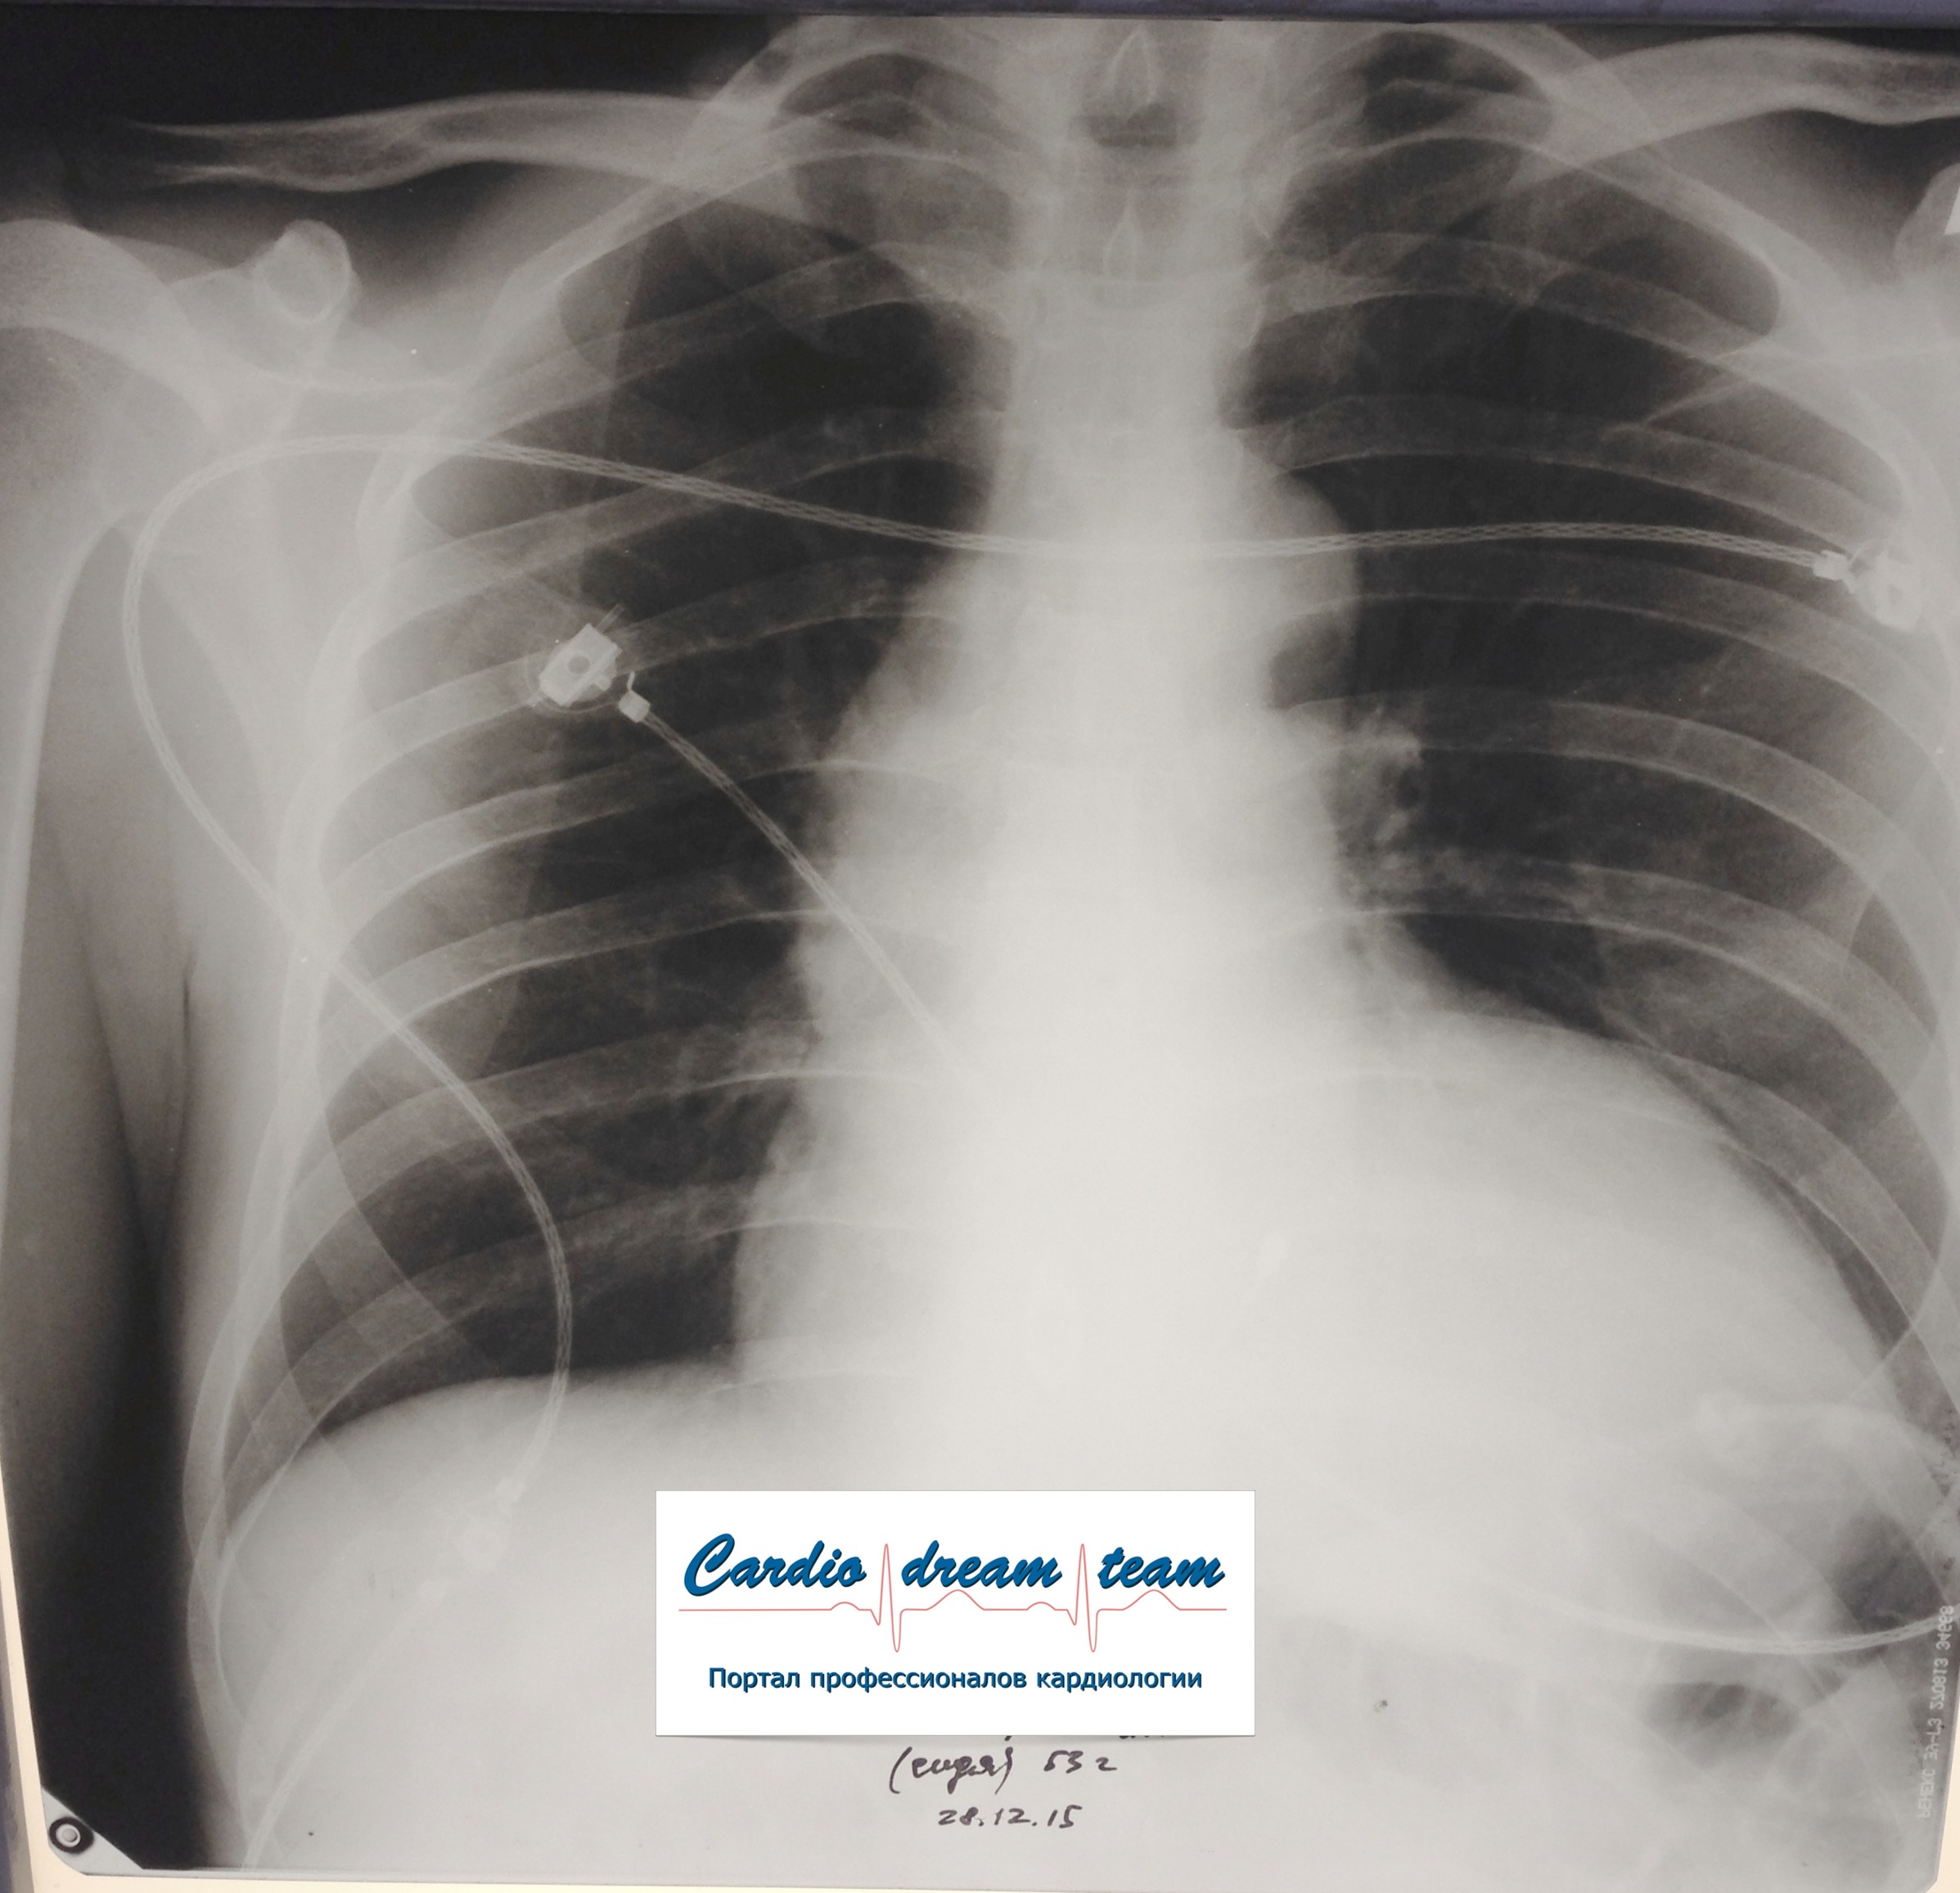

Не обсуждалась Дата 23-ИЮЛ-15 ОПИСАНИЕ: Проведена рентгенография органов грудной клетки в прямой проекции, положение лежа, условия ПИТ Легочные поля: неравномерно прозрачны за счет сосудистого обогащения, в базальных отделах с обеих сторон, отмечается сгущение легочного рисунка, за счет гиповентиляции, в плевральных полостях жидкость Легочный рисунок: Изменен по смешанному типу: обогащен за счет сосудистого компонента, деформирован за счет склероза. Корни: бесструктурны, расширены за счет сосудистого компонента, обогащены Синусы: определяется наличие жидкости по линии 5 ребра Сердце: широко лежит на диафрагме отмечается расширение границ сердечной тени влево, вправо экг-электроды. ЗАКЛЮЧЕНИЕ: Рентген-признаки 2-х стороннего гидроторакса с гиповентиляцией базальных сегментов.. Признаки застоя по МКК 2 степени (умеренно выраженный). Пневмосклероз. Р-признаки гипертрофии левого желудочка сердца. Склероз аорты.

IMG_4339--.jpg [ 717.06 KiB | Просмотров: 30239 ]